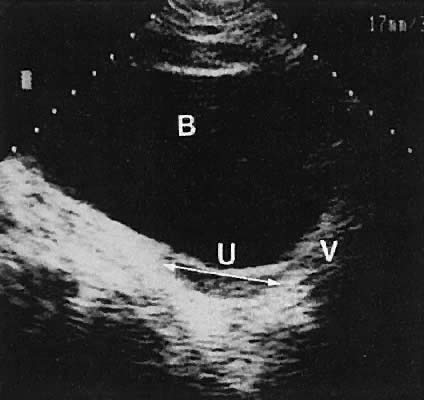

Occasionally, with overdistention of the urinary bladder, urine may accumulate in the vagina (Fig. 5). Likewise, the presence of tampons or menstrual blood may be discerned.

Fig. 5. Longitudinal transabdominal scan showing urine distending the vagina (V); the bladder (B) is overdistended.